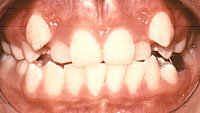

![]() |

Sau chỉnh hình |